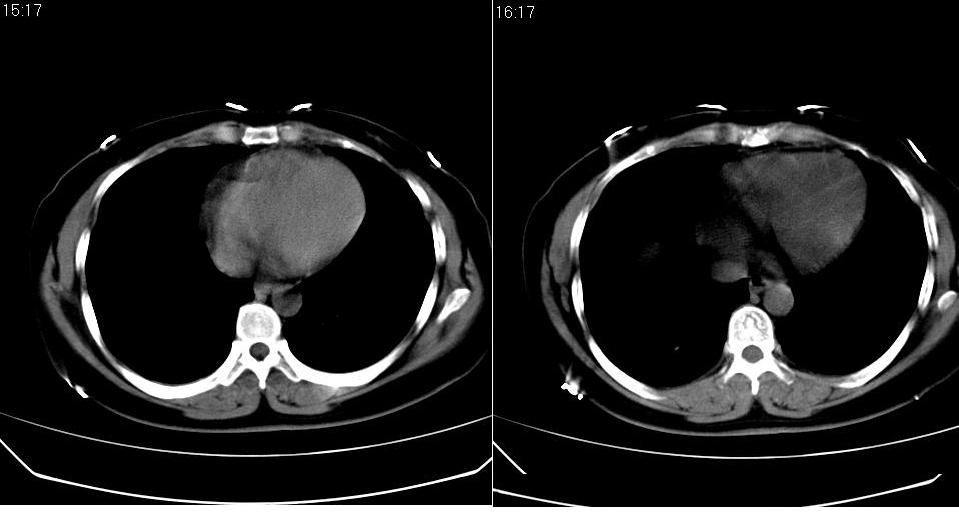

女 40岁,胸片体检发现右肺肿块,无任何症状。

下叶背段多发性小腺泡结节,考虑结核。

肺动静脉瘘可考虑,建议增强

典型结核表现

考虑右肺下叶背段继发性肺结核。